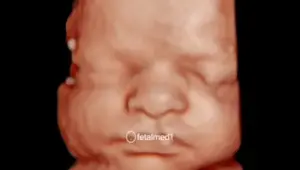

O ultrassom morfológico de primeiro trimestre é o exame mais importante do início da gestação. Realizado entre 11 semanas e 3 dias e 13 semanas e 6 dias, ele avalia detalhadamente a anatomia do feto quando o bebê mede entre 45mm e 84mm de comprimento da cabeça à nádega.

O exame pode ser realizado por via abdominal, mas em alguns casos é complementado pela via transvaginal, que permite imagens de maior qualidade e precisão diagnóstica.

• Anatomia fetal — avaliação do crânio, cérebro, coluna, membros, coração e órgãos abdominais